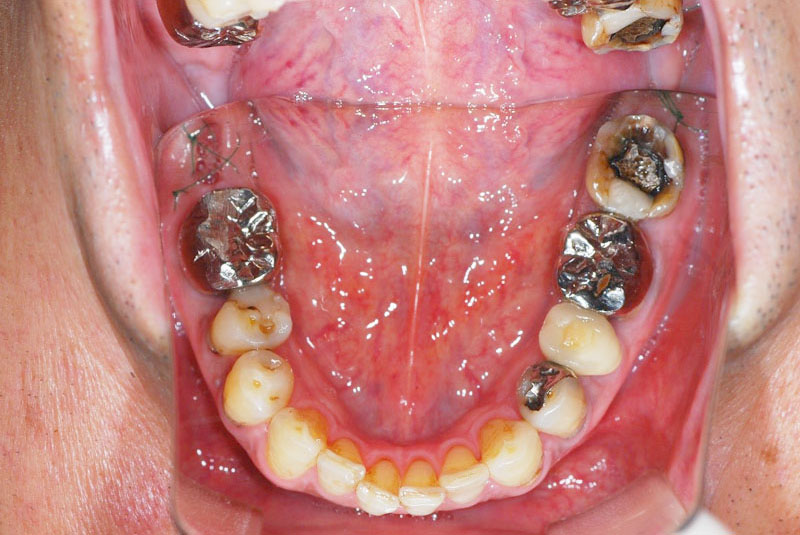

多数歯欠損のインプラント(サイナスリフト・GBR併用)

- 患者

- 50代男性

- 主訴

- インプラントができないかどうか相談。

できるだけきれいにしたい。

- 治療経過

- 前医にて上顎部分入れ歯を装着、下顎の奥歯を抜歯した状態で来院されました。また下顎の両側の臼歯の抜歯が必要と診断されたとのことでした。前医にインプラントを相談したが下顎はできるが、上顎は骨がないことを理由にインプラント不可能と診断され当院受診されました。診断の結果、下顎臼歯は保存可能、上顎臼歯部は左右上顎洞に対する骨造成(サイナスリフト)、前歯部はGBRにて骨造成を行い、インプラント埋入を行いました。

サイナスリフトはかなり専門性の高い外科処置であるため対応できる歯科医師は限られます。そのためショートインプラントや傾斜埋入で対応されることも多いですが、患者さんの年齢や希望を伺いながら当院では必要であれば積極的に行っております。その他不良補綴物の除去、根管治療、虫歯治療を行い全顎に対して審美的修復を行い治療終了までに2年を要しました。ちなみに当院では1本も抜歯は行いませんでした。保存できる歯と抜歯の必要な歯をしっかり診断することも必要です。